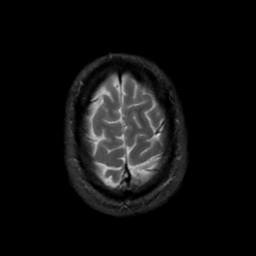

MR Study #3, February 24, 1991 -- Slice #44

[Home][Help][Clinical][Tour 1][Tour 2] Slice 44